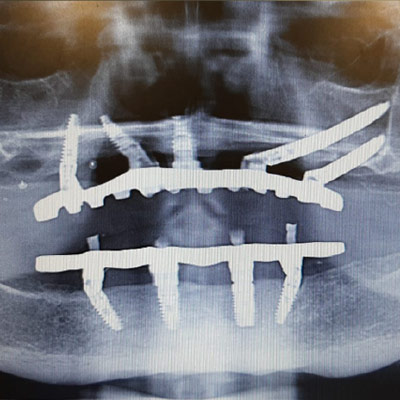

Full Arch Implant Rehabilitation

Questo corso ti prepara a gestire le riabilitazioni di una o entrambe le arcate su soli supporti implantari. Impariamo a gestire il paziente totalmente edentulo, parzialmente edentulo e quello con dentizione terminale.

All on x-procedures from A to Z.